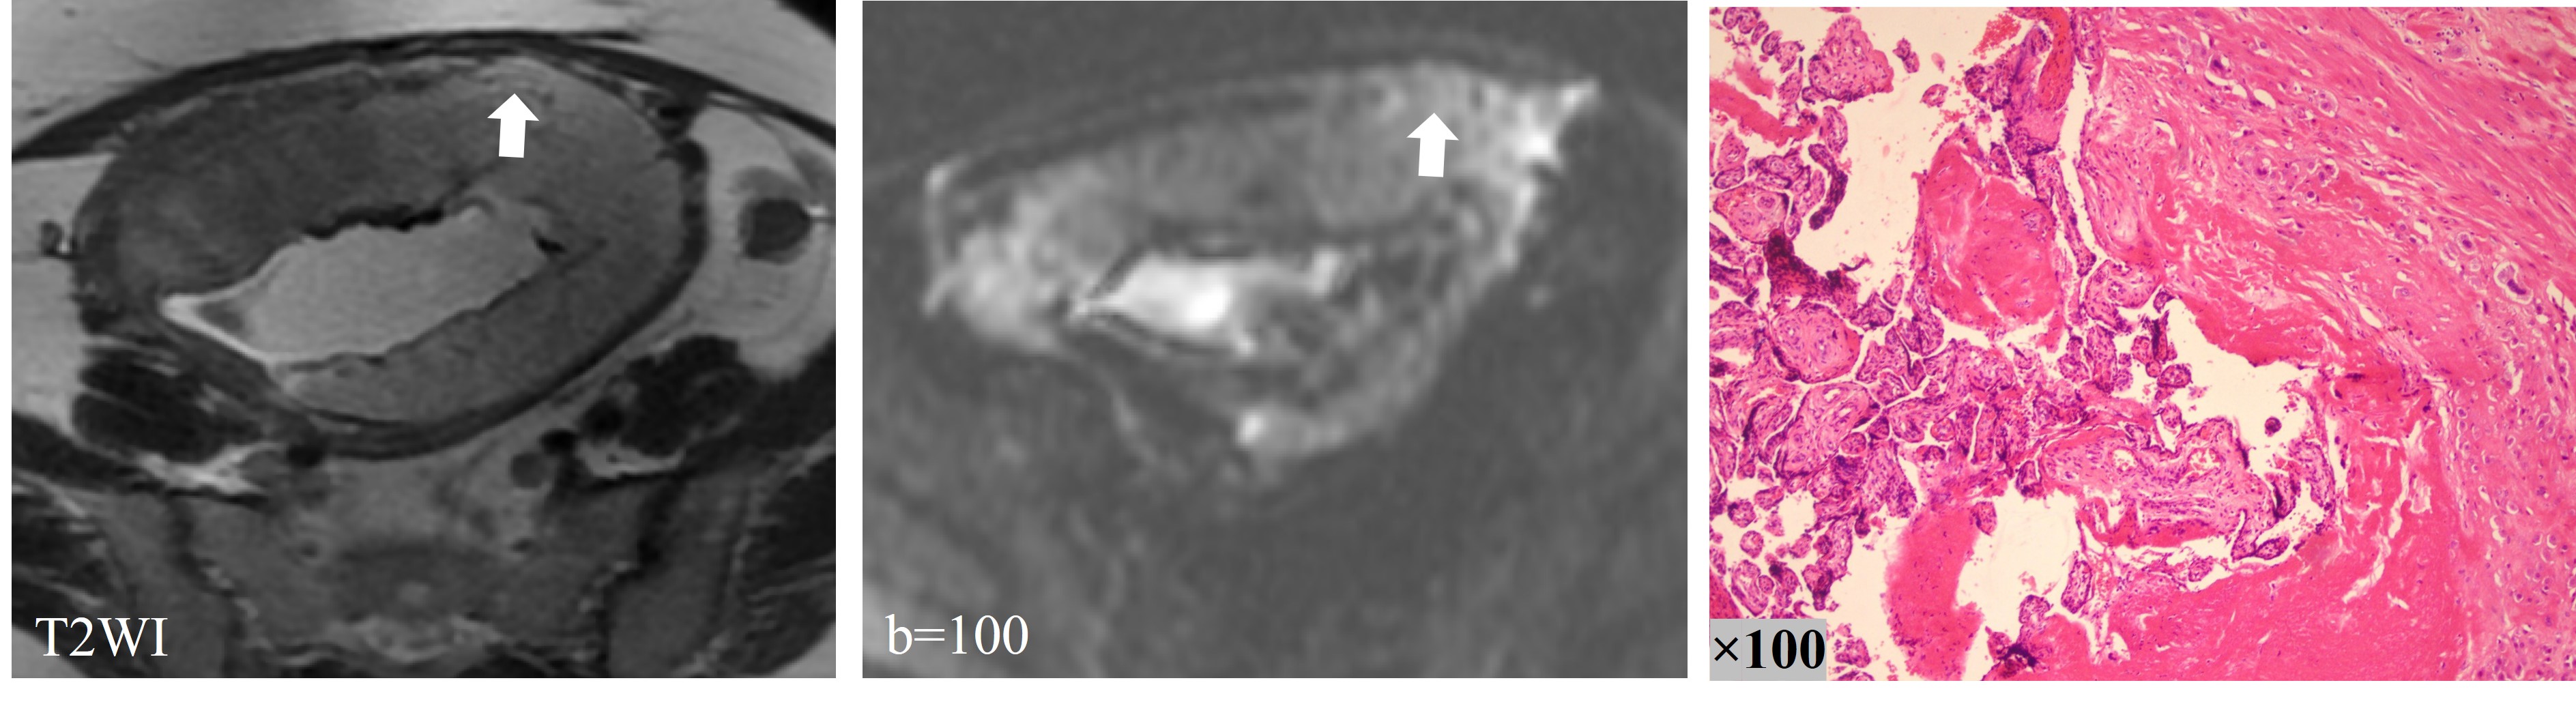

Figure 3 demonstrated three-layer structure of the placenta according to the images of pathologic tissue section. The original IVIM images clearly showed the outer myometrium as a strip of slightly high signal. There was a strip of low signal under the myometrium corresponding to the placental basal plate in the pathologic tissue section. The original IVIM image can more clearly show the myometrium as a strip of slightly high signal shadow, with a strip of low signal shadow under the myometrium corresponding to the basal layer of the placenta in the pathological section. Several short discontinuities (<10 mm in length) were seen in the low signal band of the basal layer, which was considered to be probably related to the curvature of the fibrous tissue of the basal layer (Figure 3C). The inner part of the basal plate was placental villous portion.

Figure 3. The three-layer structure of the placenta according to the images of pathologic tissue section. The large arrow showed the myometrium and the small arrow indicated placental basal plate. Black stars refered to the fibrous tissue in the placental basal plate.